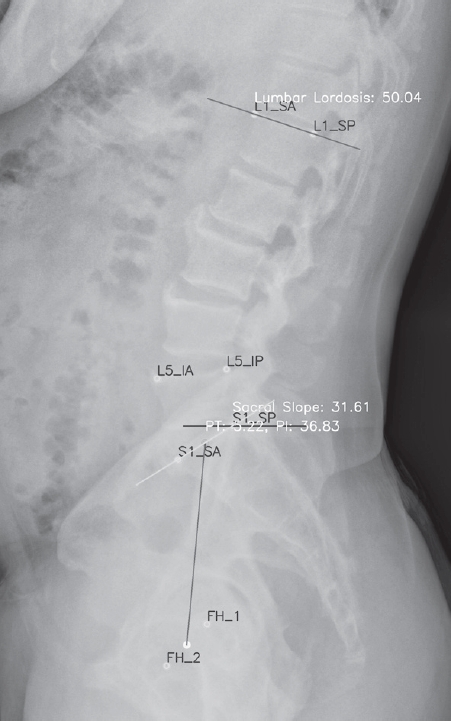

A total of 904 patients were included in the analysis. A representative image of lumbar lordosis measured by the AI-based automated model is shown in Fig. 1. The age distribution of the study population is presented in Table 1. The 60–69-year group comprised the largest proportion, with 203 patients (22.5%), followed by the 10–19-year group with 169 patients (18.7%). In contrast, the 20–29-year group had the smallest representation, with 26 patients (2.9%). Overall, a substantial number of patients were concentrated in the older adult (60–79 years). Females (548 patients, 60.6%) outnumbered males (356 patients, 39.4%).

Fig. 1.

A representative image measured by the AI-based automated measurement model. In addition to lumbar lordosis, spinopelvic parameters such as sacral slope, pelvic tilt, and pelvic incidence can also be measured.

Fig. 1. A representative image measured by the AI-based automated measurement model. In addition to lumbar lordosis, spinopelvic parameters such as sacral slope, pelvic tilt, and pelvic incidence can also be measured.